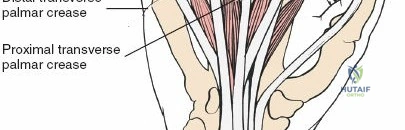

The palmar fascia, located superficial to the flexor tendons in the palm, is a dense aponeurosis important in conditions like Dupuytren's contracture. This fascial layer can obscure deeper structures and must be carefully managed during deep palmar dissection. The thenar and hypothenar eminences, as well as the transverse palmar crease, serve as important surface landmarks for guiding incisions and identifying underlying structures. The vincula tendinum (longus and brevis) are mesotenon-like structures that provide vascular supply to the flexor tendons within the sheath, and their preservation, where possible, is beneficial.

Surface landmarks guide the incision. In the digits, these include the distal phalangeal crease (just proximal to the distal interphalangeal joint), the proximal interphalangeal crease, and the metacarpophalangeal crease. In the palm, the distal palmar crease and thenar/hypothenar creases are important.

- Palmar Incision: Can be made as a curvilinear extension from the digital Bruner incision, often curving towards the thenar or hypothenar eminence, or as a transverse incision in line with the distal palmar crease. Incorporating a laceration directly into the incision is always preferred to minimize additional skin damage.